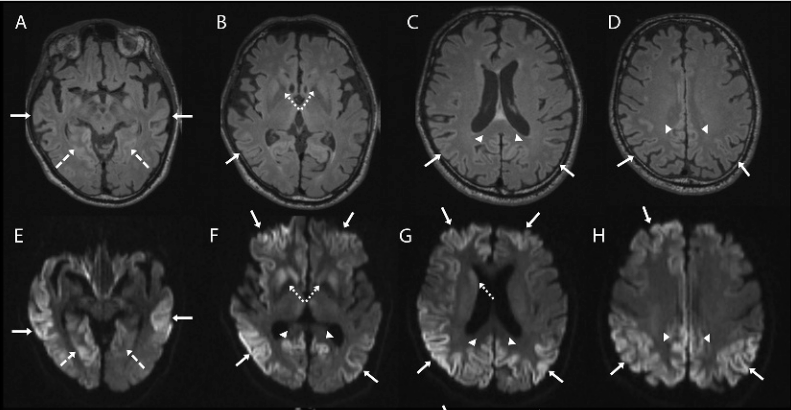

朊病毒大脑空洞

阮病毒直击大脑朊病毒的可怕之处就在于它会直接进攻人和动物的大脑